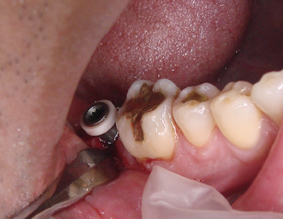

DSC01672.JPG

インプラントが歯肉の中に見えます

今回は麻酔の注射はしていません

写真の見える歯肉のくぼみに綿球で

表面麻酔を塗りました

骨ができ過ぎていたりすると

麻酔の注射が必要になることもありますが

痛いというほどのことはありません